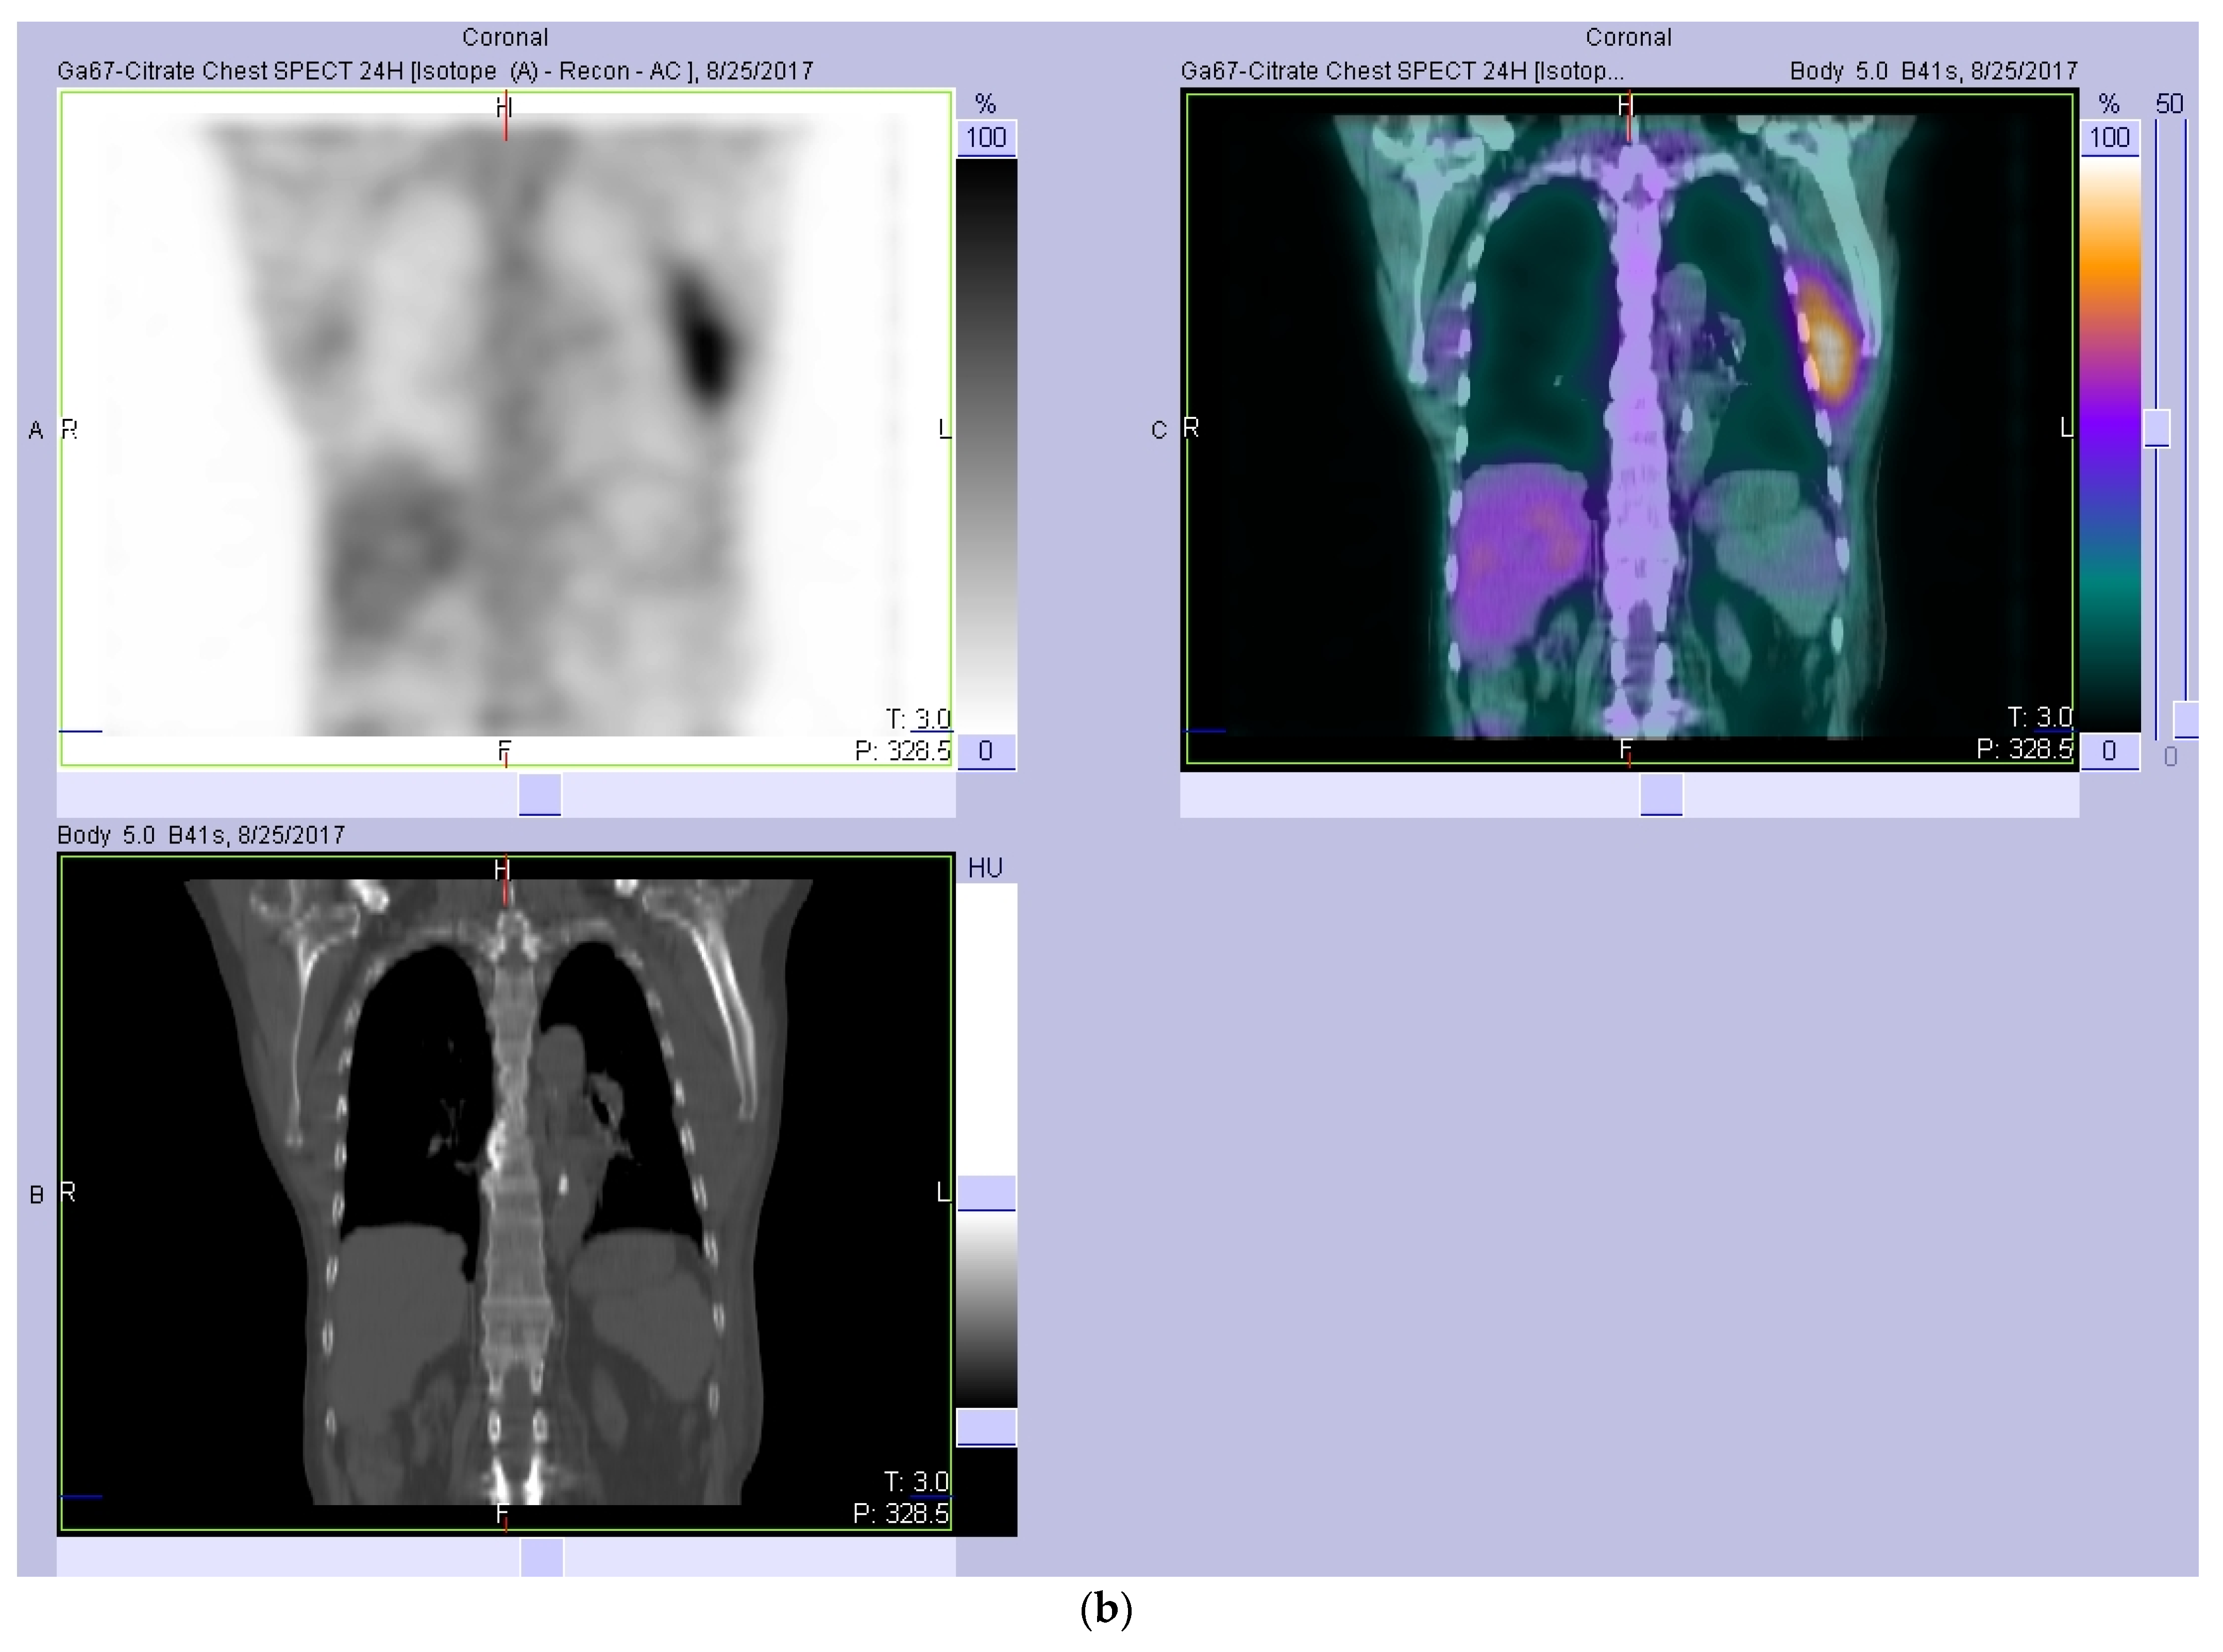

2. Case Report